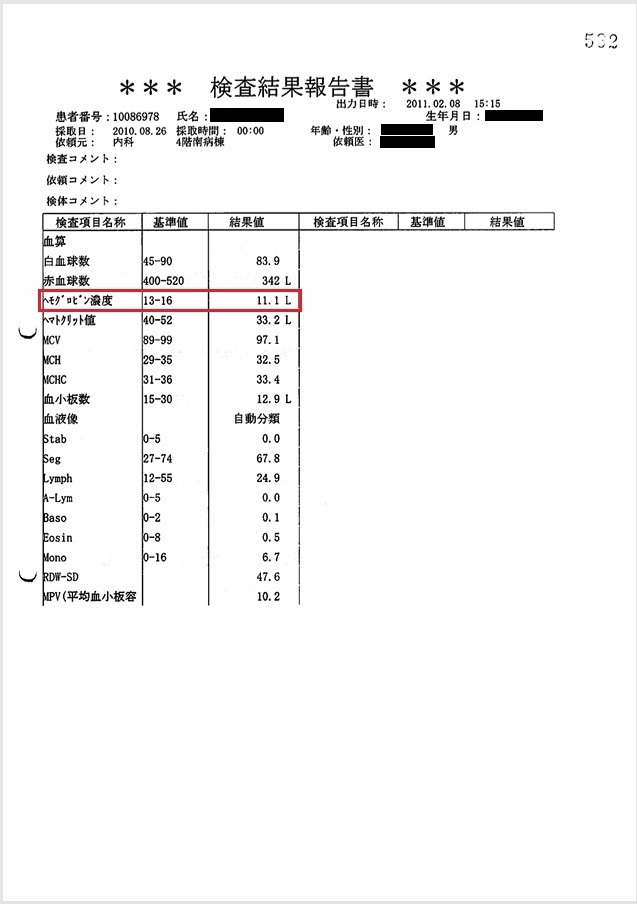

- 8月26日:Hb 11.1 g/dlで輸血開始

貧血にて輸血開始(カルテ・看護記録に記載あり)。しかし当日の血液検査ではHb 11.1 g/dlと貧血は軽度。 Hb 11.1 g/dlが本当であれば不適切診療。輸血が必要な状態であれば、Hb 11.1 g/dlは虚偽。

証拠:カルテ・看護記録・血液検査の抜粋